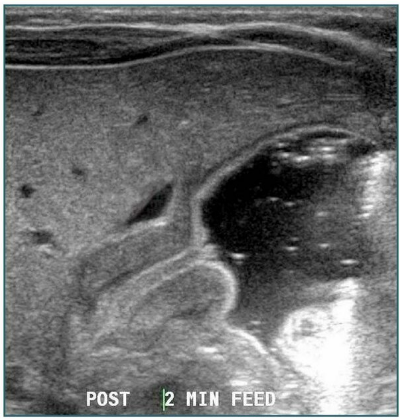

The given USG shows _____ sign and _____ sign in congenital hypertrophic pyloric stenosis